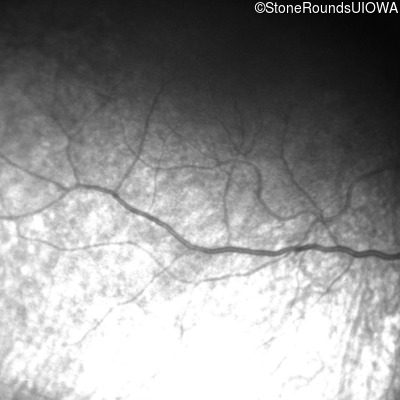

Infrared Fundus Photograph - Left - No Light Perception

Exemplar